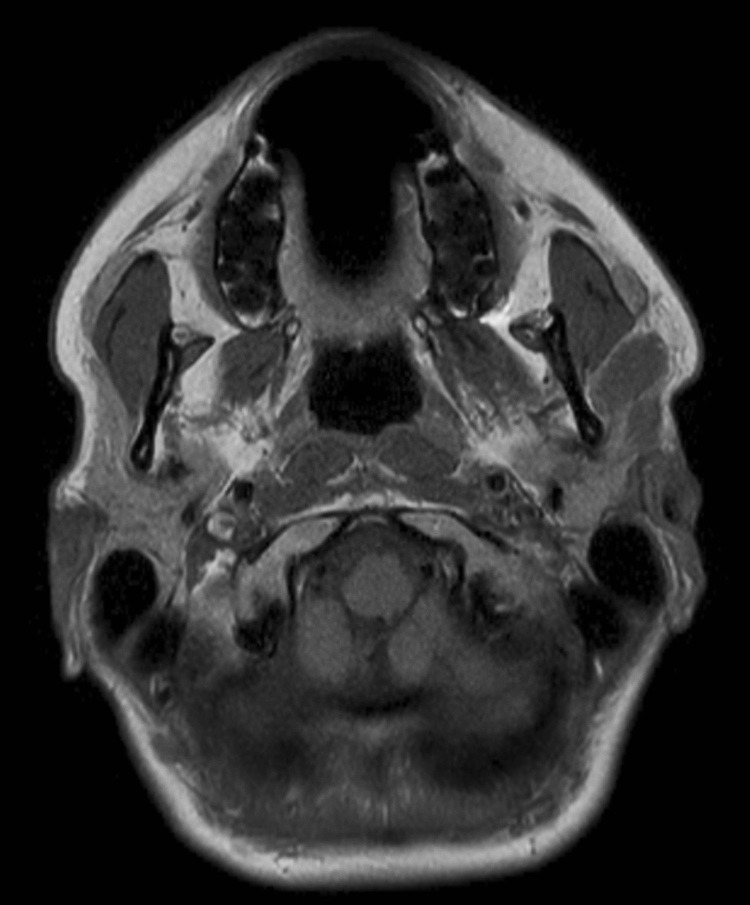

Axial T2w TSE